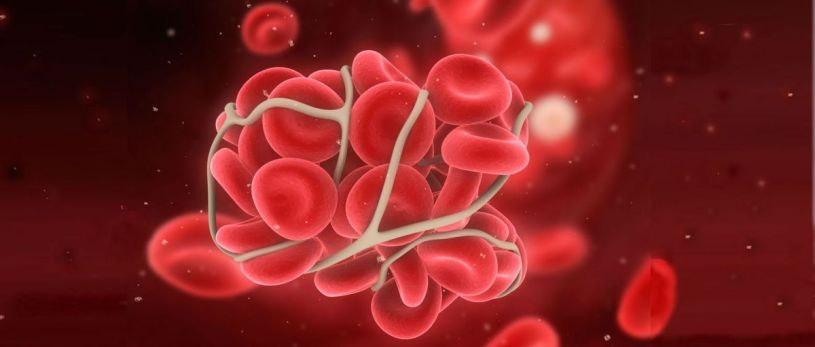

Sindrom antifosfolipid terjadi saat sistem kekebalan tubuh menyerang beberapa protein normal dalam darah, dalam hal ini salahsatunya adalah fosfolipid (komponen penting dari sistem pembekuan darah). Hal ini dapat menyebabkan penggumpalan darah di arteri atau vena, yang dapat menyebabkan komplikasi kehamilan, seperti keguguran dan lahir mati. Bekuan darah di pembuluh darah kaki dapat juga menyebabkan kondisi yang dikenal sebagai deep vein thrombosis (DVT). Kerusakan akibat penggumpalan darah di organ tubuh lain, seperti ginjal, paru atau otak, bergantung pada luas dan letak gumpalan. Misalnya, bekuan di otak bisa menyebabkan stroke. Tidak ada obat untuk sindrom antifosfolipid, tapi perubahan gaya hidup, diet dan obat-obatan tertentu dapat mengurangi risiko penggumpalan darah.

- Bekuan darah di kaki (DVT), yang juga bisa sebabkan sumbatan di paru apabila terlepas (emboli paru).

Pada sindrom antifosfolipid, pembekuan darah tidak normal karena tubuh secara keliru menghasilkan antibodi yang menyerang fosfolipid, sejenis lemak yang memainkan peran penting dalam pembekuan. Antibodi adalah protein yang biasanya melindungi tubuh terhadap penyerang, seperti virus dan bakteri.

- Seseorang dapat mengalami kejadian penggumpalan berulang dalam waktu singkat, menyebabkan kerusakan progresif pada banyak organ (sindrom antifosfolipid katastrofik).